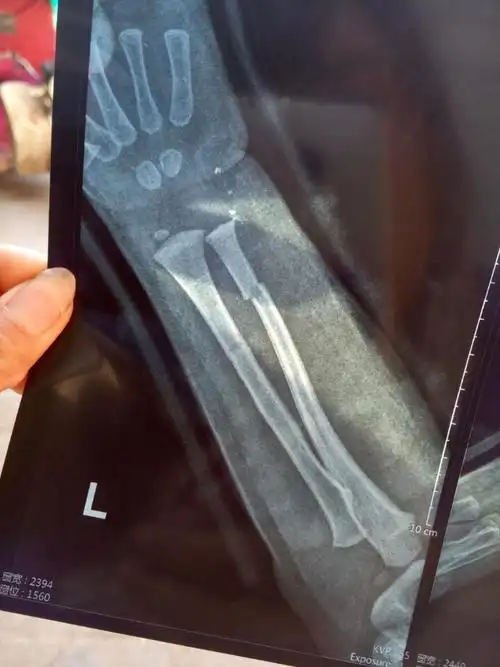

小孩2岁左臂骨折,下面是拍得片,感觉接的有点错位,但医生说没事说长长